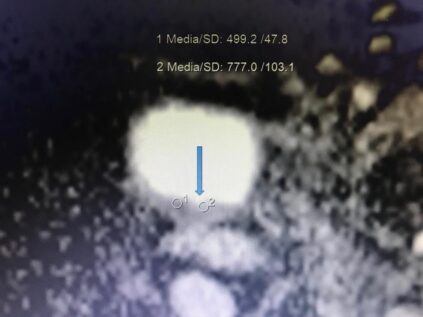

RM Biparamétrica de vejiga. (Cáncer de vejiga)

Femenina de 80 años, con prótesis en cadera derecha. Antecedente de IRC. No es posible realizar estudio de angiogénesis, por presentar TFG de 15ml/min y por consiguiente no administramos contraste endovenoso. Sin embargo, con las secuencias morfológicas y funcionales de la RM, es posible hacer el diagnóstico y el estudio de extensión de la lesión. ( T2 N0 M0. Estadio II). La Difusión -RM, nos permite determinar la celularidad tumoral y eventualmente monitorear la respuesta al tratamiento.